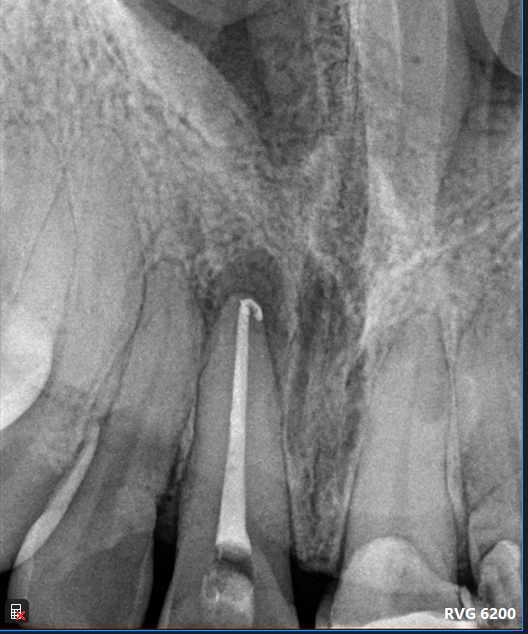

Case: RCT on Tooth #9

13-year-old male, healthy, no medications, no known allergies.

Dx: Necrotic pulp and acute apical abscess (#9).

Tx: Root canal therapy initiated.

Reflection

This case involved a necrotic tooth with an open apex and blunderbuss canal. Achieving apical control was a challenge due to the lack of a natural stop. Apexification was considered, but we managed to adapt a large master cone (#60), trimming the tip to get a snug fit and achieve proper tug-back, allowing us to complete obturation successfully.